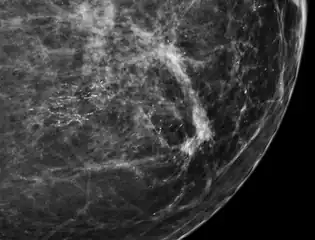

Microcalcifications are tiny deposits of calcium salts that are too small to be felt but can be detected by imaging.[1]

They can be scattered throughout the mammary gland, or occur in clusters. Microcalcifications can be an early sign of breast cancer. Based on morphology, it is possible to classify by radiography how likely microcalcifications are to indicate cancer. [2]

In breast